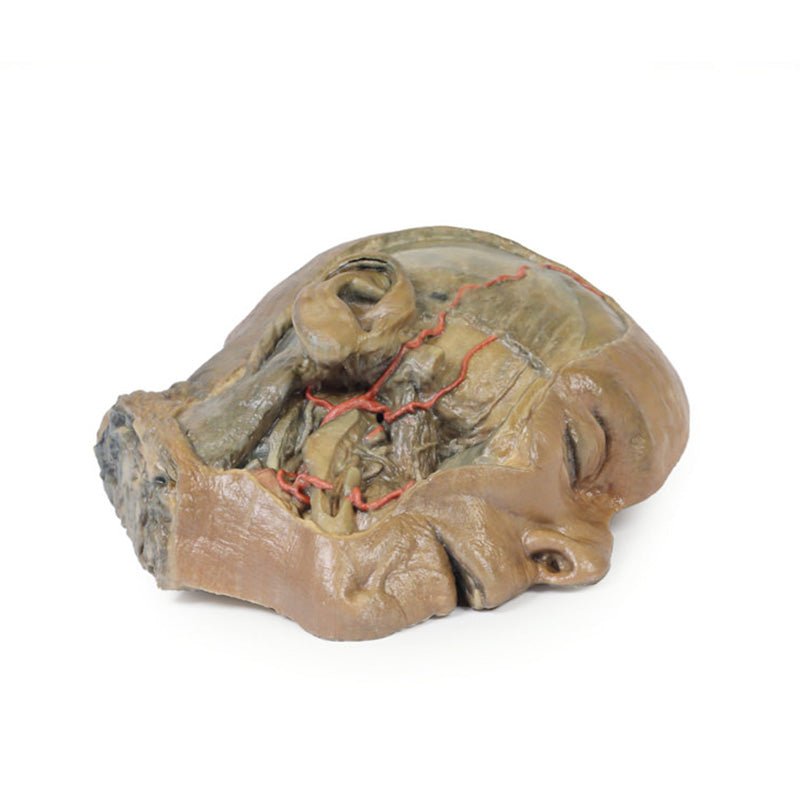

3D Printed Sagittal Section of Head with Infratemporal Fossa Dissection

This 3D model provides a combined midsagittal section through the head and

superior neck coupled with a deep dissection into the infratemporal fossa

region and superficial dissection of the scalp.

On the opposing side of the model, a superficial and deep dissection has

opened a large window into the anatomy of the lateral scalp and infratemporal

fossa. Across the scalp there is a well preserved posterior auricular nerve

and superficial temporal artery highlighted on the superficial surface of the

temporalis muscle. Anteriorly, the temporalis has been dissected to expose

the deep temporal arteries arising from across the maxillary artery.